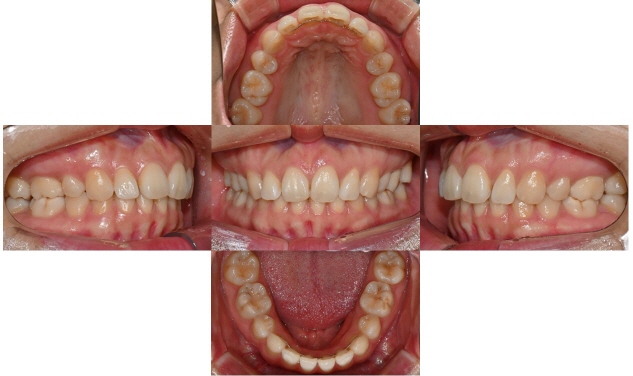

2025.5.20 교정치료 완료

과개교합 치료 전후 사진 비교

총 3달 정도의 치료기간 동안 오른쪽 틀어진 앞니가 가지런하게 배열되었고 치아사이 공간도 타이트하게 닫을 수 있었습니다. 또한 위아래 앞니가 서로 세게 닿지 않도록 위 앞니를 위로 살짝 올려주어 과개교합을 개선하였습니다.

과개교합의 경우 일반 교정장치로 부분교정하기에는 쉽지 않은 치료과정이나, 인비절라인의 경우 부분교정으로도 어느 정도의 과개교합의 개선은 충분히 가능합니다. 치료 마무리 후 송곳니까지 고정식 유지장치를 붙이고 가철식 유지장치를 제작하여 다시 틀어지거나 벌어지지 않도록 하였습니다.